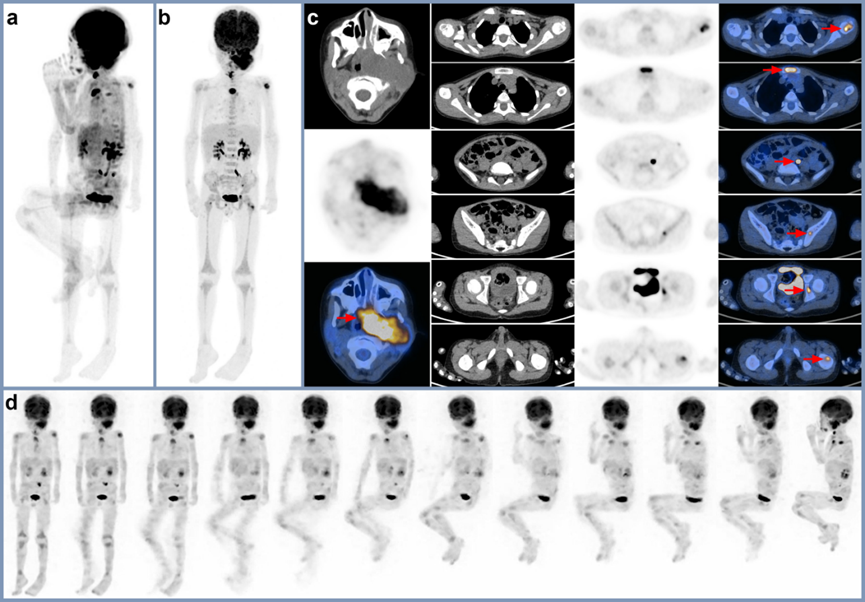

彬彬在非镇静情况下大幅不自主运动时的临床扫描诊断图像

PET-CT在肿瘤分期、复发和治疗反应评估中发挥着重要作用。与其他传统的影像学手段相比,PET-CT显示出更好的敏感性和特异性。凭借接诊数千例儿童肿瘤患者的丰富临床经验,基于世界首台Total-Body PET-CT uEXPLORER的超高灵敏度性能,这一次,在彬彬不自主变换从仰卧到右侧卧的情况下,中山大学肿瘤防治中心樊卫主任团队仅截取仰卧段的数据进行图像重建,依然拿到了清晰的PET肿瘤诊断影像,创新突破解决了儿童肿瘤患在扫描中不自主运动的问题,同时避免了重复扫描。“目前,针对儿童肿瘤领域,我们已经在国际核医学顶级期刊中发表了多篇科研论文,希望我们的努力可以为创新儿童肿瘤诊疗方法、救治更多肿瘤患儿做出贡献。”中山大学肿瘤防治中心核医学科主任樊卫说道。